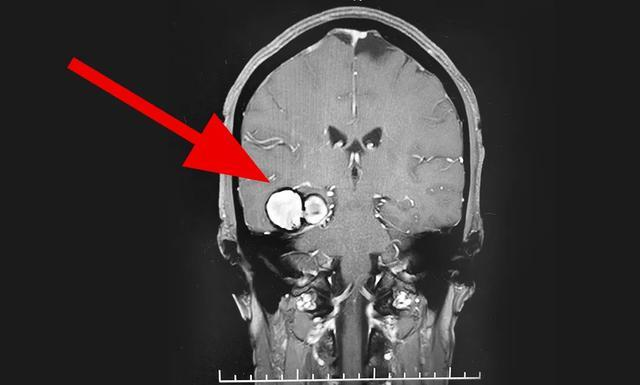

经检查发现,老尹的脑内有个海绵状血管瘤,这个瘤不仅破裂出血,还压迫了脑干,医生紧急安排手术。手术做的很漂亮,过程也很顺利,老尹术后恢复良好。